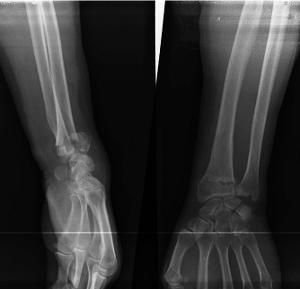

外傷使局部腫脹疼痛畸形骨折遠端向掌側移位腕,呈屈曲狀橈骨遠端向背側突出正側位腕關節X線片可明確診斷。

拍腕關節正側位X線片可確定診斷。

X線片上,典型的畸形是橈骨之遠折端連同腕骨向掌側移位,向近側移位。尺骨莖突可受累或不受累。很少有嵌入骨折,掌側骨皮質常有粉碎。